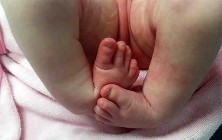

An infant with idiopathic clubfoot is being treated with the Ponseti method of serial casting.

The forefoot has been successfully abducted to 60 degrees, and the heel is in valgus. However, the foot remains in 20 degrees of equinus. What is the most appropriate next step in management?